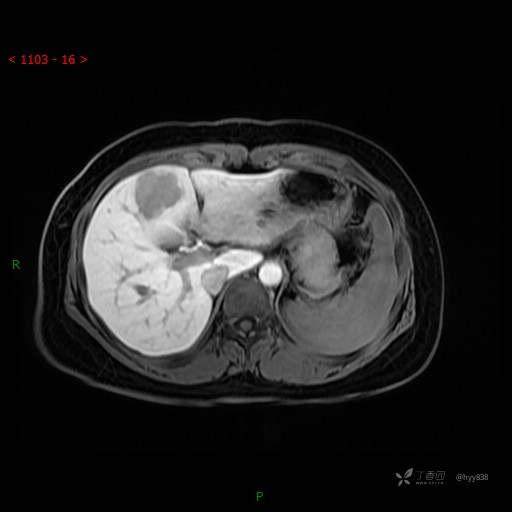

延迟肝胆期